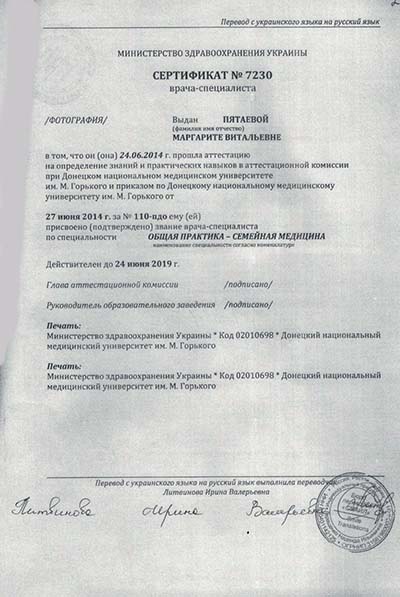

Лицензии и сертификаты

Лечение в нашей клинике анонимно, поэтому никто не узнает, что вы проходите или проходили лечение в нашем наркологическом центре.

Лицензии и сертификаты нашей клиники

Медицинские услуги оказываются ООО "ЮгЭкоСервис+" по лицензии ЛО-61-01-008143 от 28.12.2021 г.